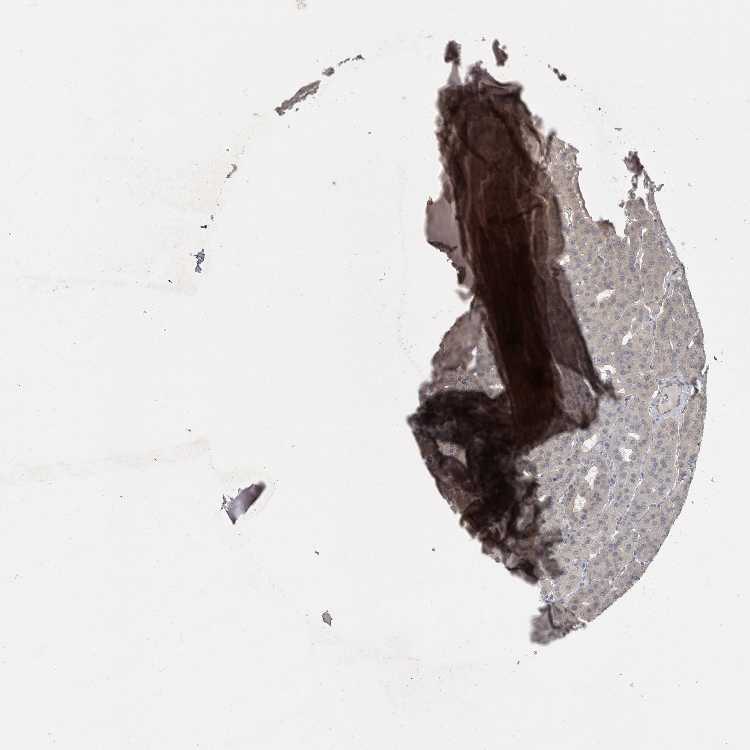

PARATHYROID GLAND - Antibody stainingi

Antibody staining in the annotated cell types in the current human tissue is reported as not detected, low, medium, or high, based on conventional immunohistochemistry profiling in selected tissues. This score is based on the combination of the staining intensity and fraction of stained cells.

Each image is clickable and will lead to virtual microscopy that enables deeper exploration of all samples and also displays staining intensity scores, fraction scores and subcellular localization as well as patient and tissue information for each sample.

Antibody HPA027726Antibody HPA075591

Glandular cells MediumHigh